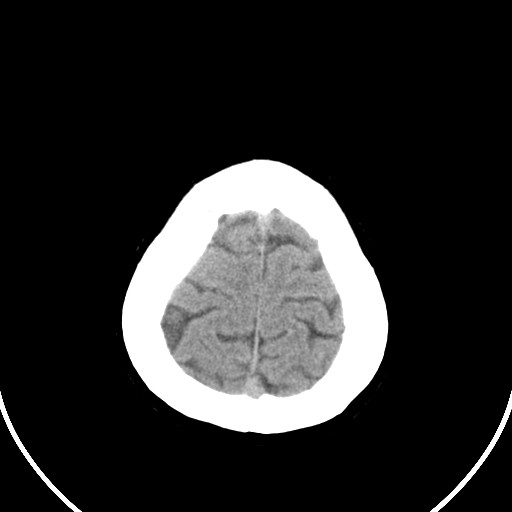

标题: CT21850:女,56岁,右中指淤肿,右手麻痹1天

女,56岁,右中指淤肿,右手麻痹1天

右侧侧脑室旁脑白质腔隙性脑梗死。

右侧基底节多发小梗塞

作者: huangyinshan    时间: 2009-8-25 15:37

右基底结区腔梗

右侧基底节区腔隙性脑梗塞

右侧基底节多发腔梗!

双侧侧脑室额角旁对称性略低密度影,边缘模糊,无占位效应,考虑轻度脑白质稀疏症(病人有高血压吗).,右枕叶低密度影多为伪影,不放心薄扫一下.

考虑脑白质病。

考虑脑白质病

右枕叶条状低密度影不应该忽略可能极具意义